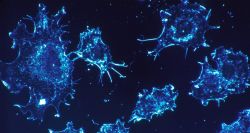

Cancer au Liban : armes modernes, tueur toujours en liberté

Makram Haddad 04/02 08:00 - Lecture : 6 minute(s)

Cancer Liban\ Marwan Ghosn Tabac USJ

À l’échelle mondiale, les derniers bilans consolidés et comparables estiment autour de 20 millions le nombre de nouveaux cas annuels et près de 10 millions de décès. Au Liban, les chiffres consolidés les plus récents disponibles (incidence et mortalité) restent lourds, avec un poids important des cancers du sein chez la femme et du ...